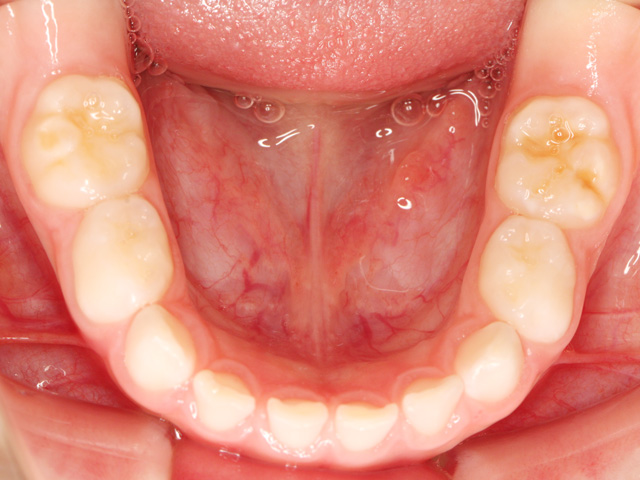

乳歯と永久歯が混在している段階を「混合歯列期(こんごうしれつき)」と専門的にに呼びますが、この段階で歯列不正があった場合に、顎の成長を活かしつつ歯並びの改善を同時に行う治療をこのように呼びます。

- 1.第一期治療完了時に残っていた乳歯が全て永久歯に生え変わり、永久歯列であること。

- 2.乳歯から永久歯に生え変わりつつある段階で、歯列不正が新たに生じて矯正治療が必要な場合。